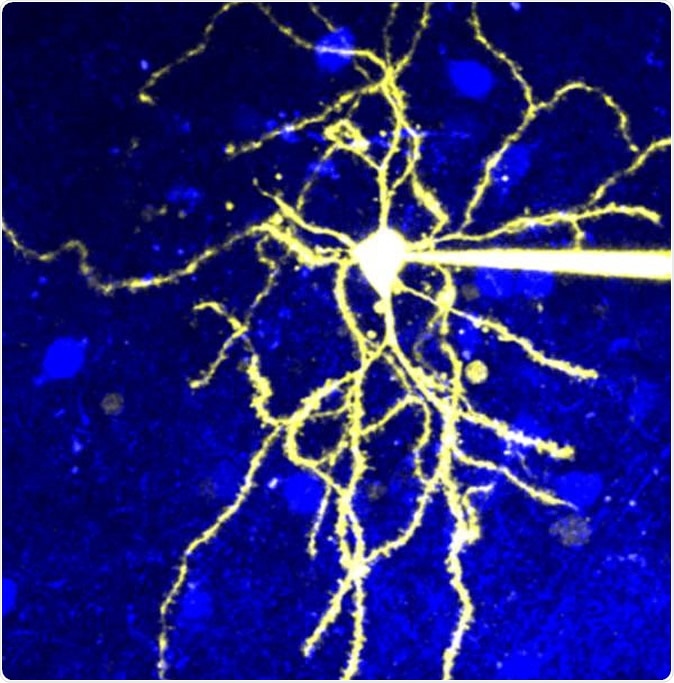

Microscopic image of a neuron that expresses D2R. Image Credit: © 2020 Yagishita et al.